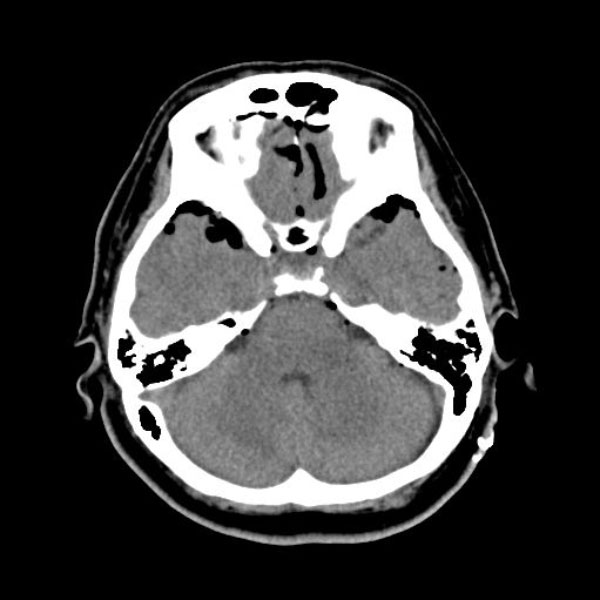

587

大阪府の病院

'26年4月

50代

左顔面痙攣

手術前